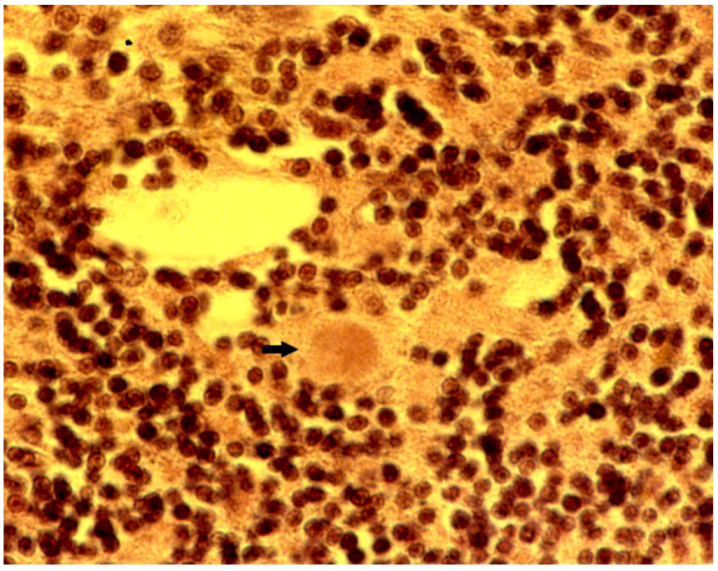

8. Neuropathology

- Biernat, W.; Liberski, P.P.; Guiroy, D.C.; Yanagihara, R.; Gajdusek, D.C. Proliferating cell nuclear antigen immunohistochemistry in astrocytes in experimental Creutzfeldt-Jakob disease and in human kuru, Creutzfeldt-Jakob disease and Gerstmann-Sträussler-Scheinker syndrome. Neurodegeneration 1995, 4, 195–201. [Google Scholar] [CrossRef]

- Liberski, P.P.; Sikorska, B.; Lindenbaum, S.; Goldfarb, L.G.; McLean, C.; Hainfellner, J.A.; Brown, P. Kuru: Genes, cannibals and neuropathology. J. Neuropathol. Exp. Neurol. 2012, 71, 92–103. [Google Scholar] [CrossRef]

- Hainfellner, J.; Liberski, P.P.; Guiroy, D.C.; Cervénaková, L.; Brown, P.; Gajdusek , D.C.; Budka, H. Pathology and immunohistochemistry of a kuru brain. Brain Pathol. 1997, 7, 547–554. [Google Scholar] [CrossRef]